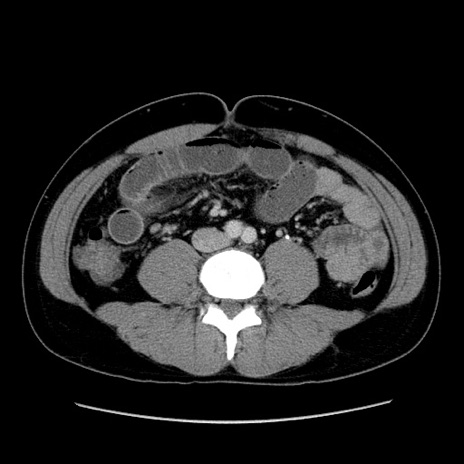

冠状断像

【症例】30歳代男性

【主訴】腹痛、嘔吐

【現病歴】昨晩から突然の腹痛あり、その後嘔吐、軟便も出現。腹痛が改善しないため救急搬送となる。2日前にしめ鯖の食事歴あり。

【身体所見】意識清明、苦悶様、BP 135/90mmHg、BT 35.7℃、腹部:平坦、やや硬、心窩部〜臍部に自発痛、圧痛あり、筋性防御+、反跳痛-

【データ】WBC 8100、CRP 0.57